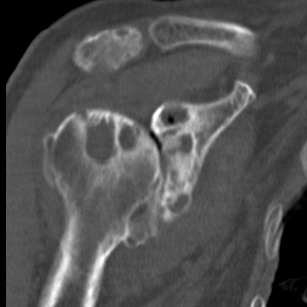

Walch classification glenoid morphology

Type A - centred humeral head, concentric wear, no humeral head subluxation

A1: minor central erosion

A2: major central erosion with humeral head protrusion

Type B - posterior subluxation of the humeral head, with biconcave glenoid and asymmetric wear

B1: narrowing of the posterior joint space

B2: biconcave glenoid with posterior rim erosion and retroverted glenoid

B3: monoconcave glenoid with > 15° retroversion or >70% posterior humeral head subluxation or both

Type C

C1: dysplastic glenoid with >25° retroversion

C2: biconcave, posterior bone loss, posterior translation of the humeral head

Type D: glenoid anteversion or anterior humeral head subluxation <40°

Type A2 Type B1

Type B2 Type B3

Type B3